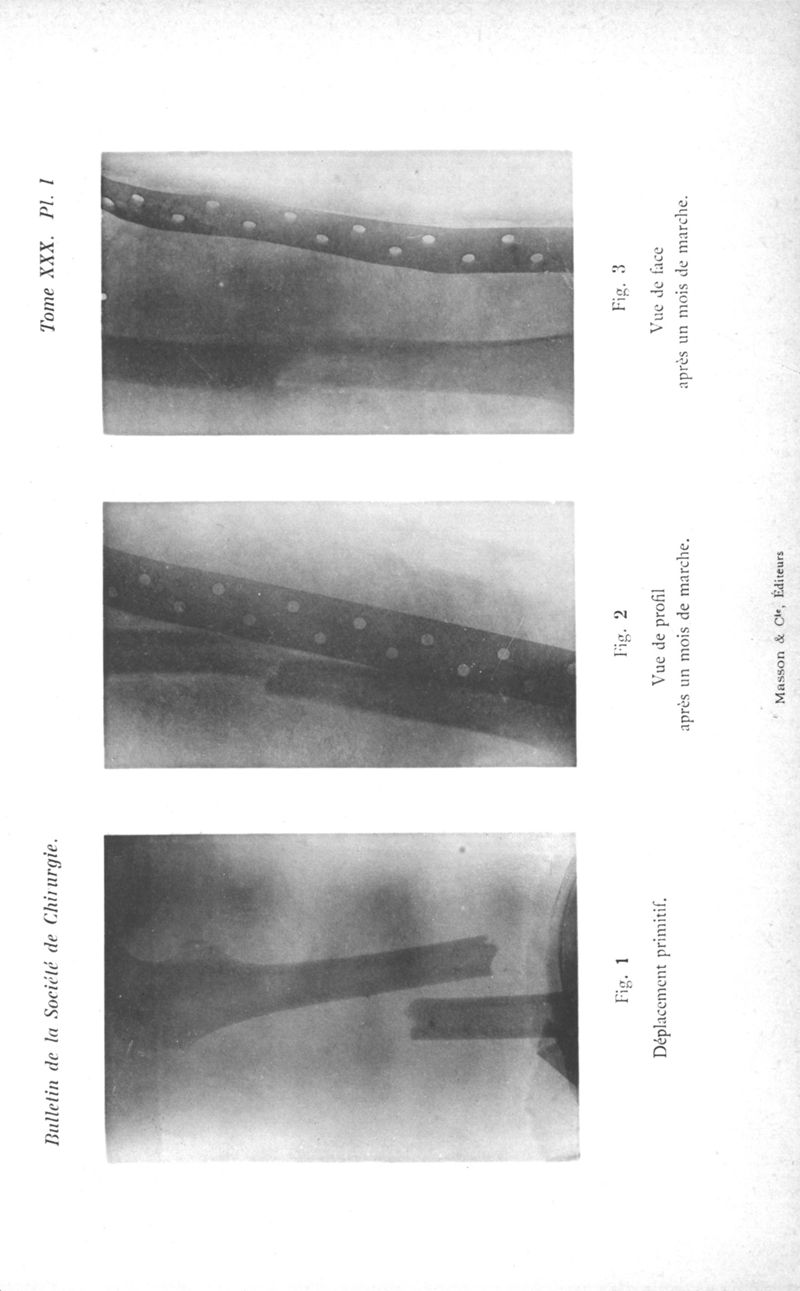

Bulletins et mémoires de la société de chirurgie de Paris

Tome XXX, 1904. - Paris : Masson, 1904.